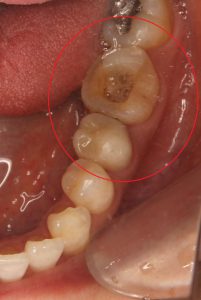

【術前】

【30代女性 主訴:左下の歯茎の腫れ】

検査の結果、治療途中だったこともあり、状態が悪く

歯を残すことが難しくありました。